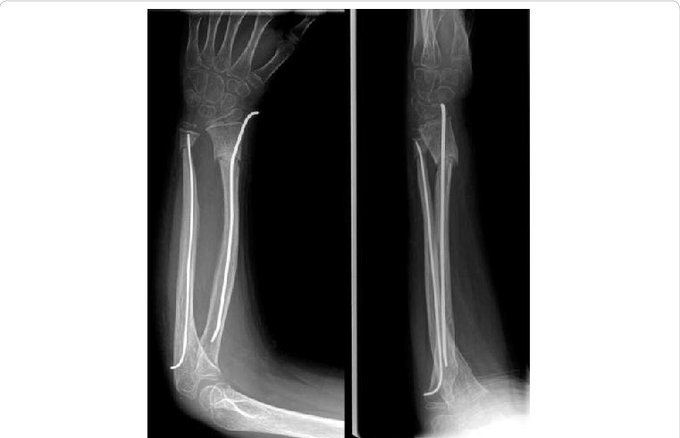

The Nancy Nail, an elastic stable intramedullary nail used in paediatric fractures, was described in the early 1980s by JP Metaizeau at the Children’s Hospital in Nancy, France (hence the name). Thanks for your tweet that made me aware of this nail!